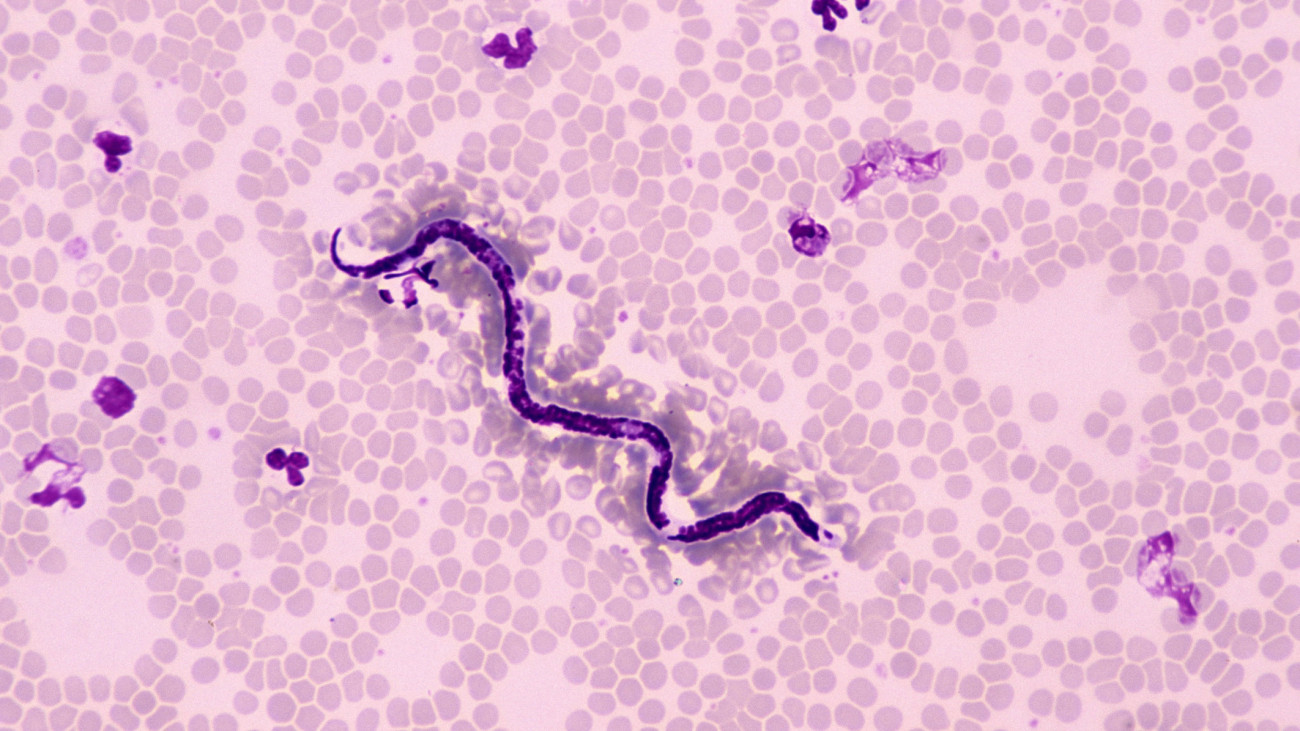

Magyarországon is mind gyakrabban fordul elő egy állatról emberre terjedő, galandféreg okozta betegség, az echinococcosis – hívja fel a figyelmet a Semmelweis Egyetem az MTI-hez szerdán eljuttatott közleményében.

Magyarországon is mind gyakrabban fordul elő egy állatról emberre terjedő, galandféreg okozta betegség, az echinococcosis - hívja fel a figyelmet a Semmelweis Egyetem az MTI-hez szerdán eljuttatott közleményében. A Sürgős figyelmeztetés jött: Súlyos fertőzés terjed Magyarországon, egyre több a beteg bejegyzés először Most Hír -én jelent meg.

Dél-Magyarországon is egyre gyakrabban bukkan fel egy emberre is veszélyes galandféreg

A féreg fő célpontjai a rókák, sakálok, de sajnos előfordul, hogy emberben is kikötnek, és olyankor elég nagy a baj.